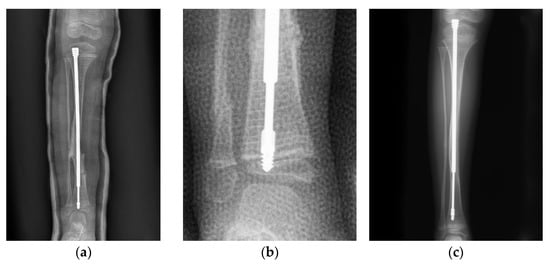

A 4-year-old male with type III OI presented as a classic model of insufficient depth of purchase and excessive bowing of the tibia (Figure 5). When axial force is applied to the limbs with excessive bowing, there will be an uneven force on the concave and convex sides, leading to delayed union (Figure 5a–c). Correction of the bowing with adequate osteotomy (or osteoclasis) before FD nail insertion is crucial (Figure 5d,e).

Figure 5. Lateral radiograph of the lower leg of a 4-year-old male post FD nail implantation. (a) There was insufficient depth of purchase into the epiphysis, and the position of the nail was anterior to the center of the epiphysis due to excessive bowing of the tibia. (b) As the patient grew, migration of the male implant (distal tibial nail pulled out of the epiphysis) was noted 2.5 years after implantation. (c) Excessive bowing resulted in uneven force applied to the concave and convex sides, which caused thickening of the cortex on the concave side and delayed union on the convex side. The aim of revision surgery was to correct bowing of the tibia with sufficient depth of purchase. (d) We corrected the bowing with adequate osteoclasis (arrow) before FD nail insertion. The position of the nail was at the center of the epiphysis in the lateral view after correcting for excessive bowing. (e) Good position of the FD nail and bone healing during regular follow-up.